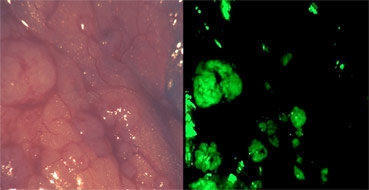

Làm khối u phát sáng có thể giúp bác sĩ loại bỏ ung thư dễ dàng